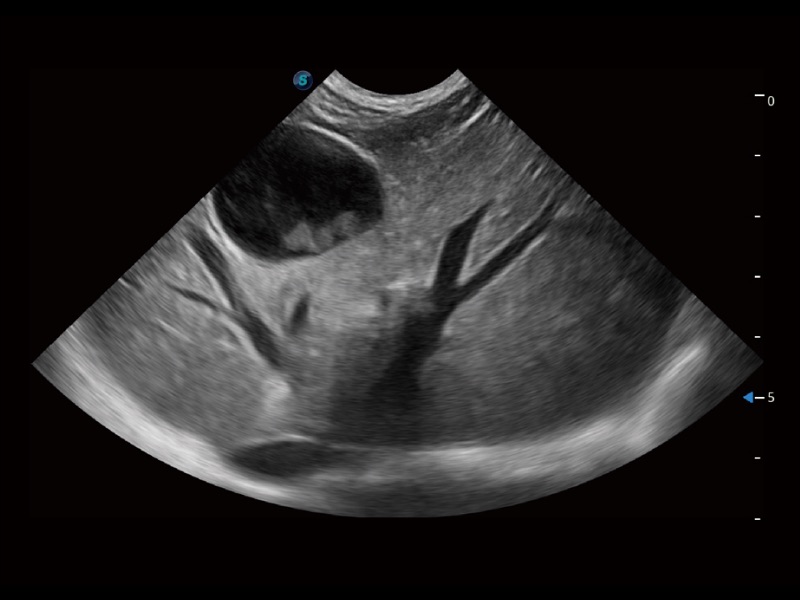

大型犬、馬科、農(nóng)場動物及大型異寵動物

ProPet 70 全新的動物超聲智能軟件和豐富的探頭群,為動物醫(yī)生提供了高清晰度和精細(xì)分辨率的圖像,無論在寵物、馬科、畜牧還是實(shí)驗(yàn)室動物等應(yīng)用中都可以輕松應(yīng)對,為您的日常工作帶來滿意的體驗(yàn)。